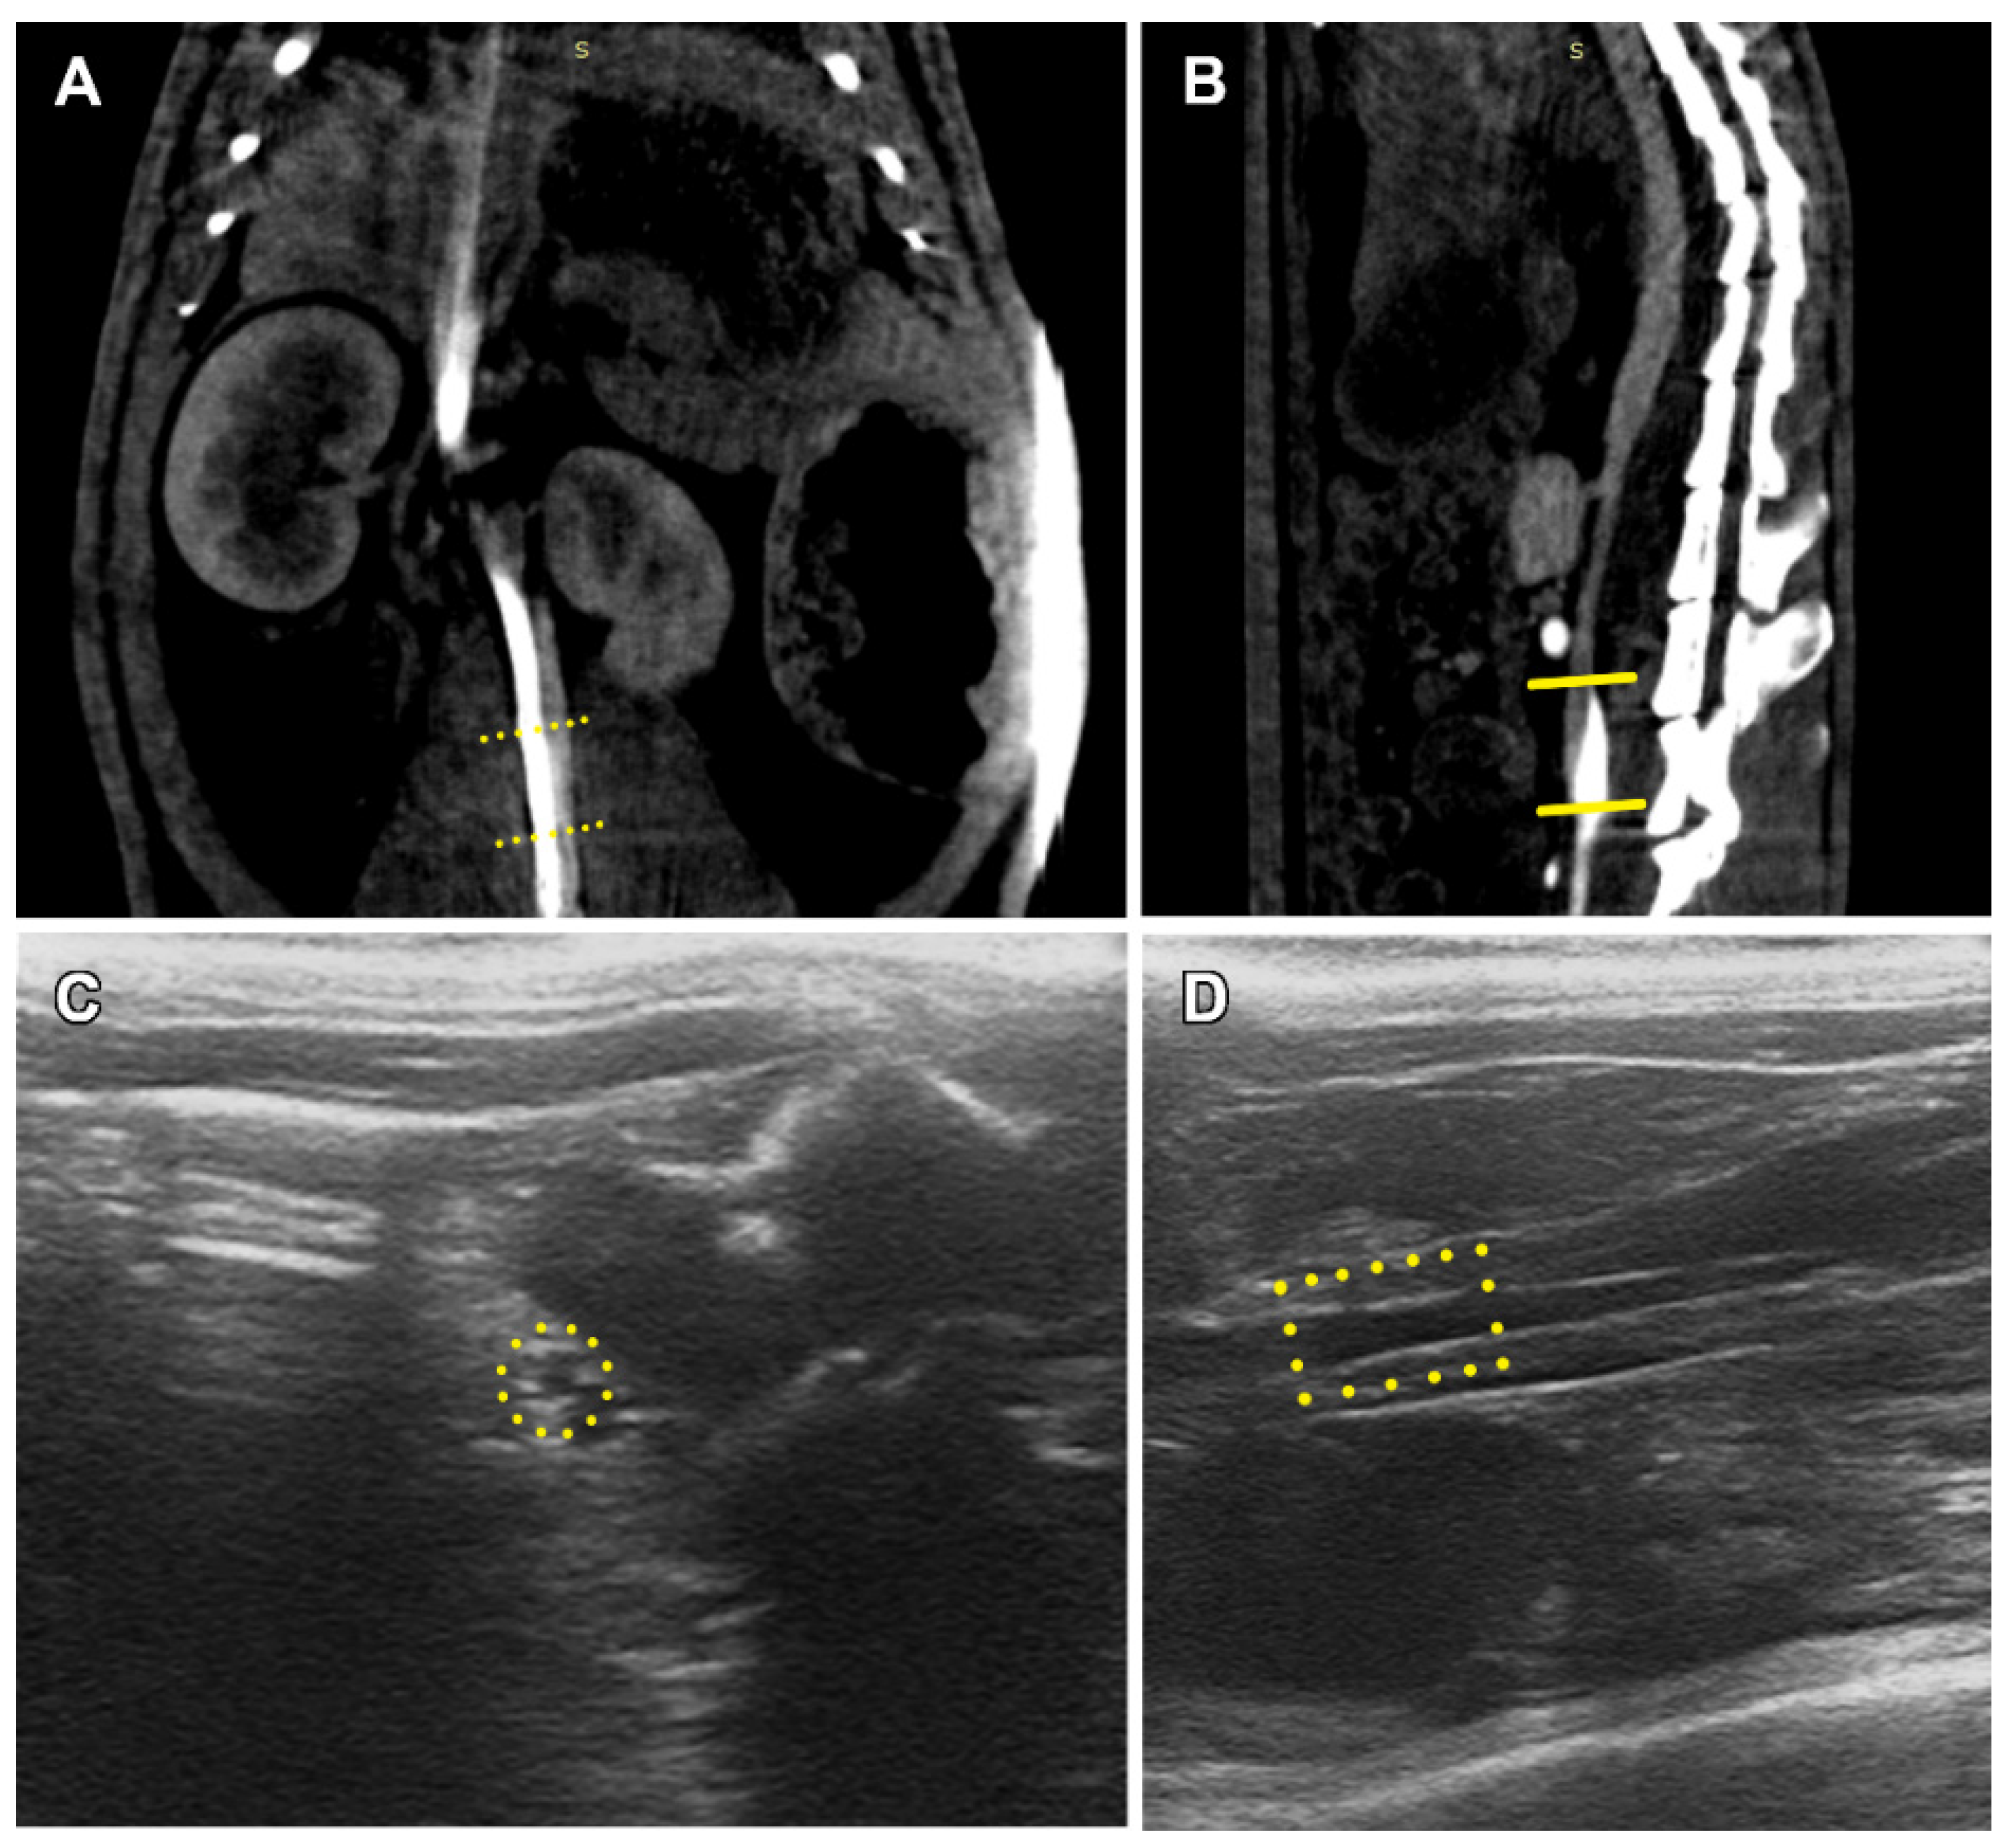

2.6. Angiography

2.7. Ultrasound Diagnostic

3.2. PCL Graft Observation in Dynamics

3.3. PCL Graft Transformation in Dynamics